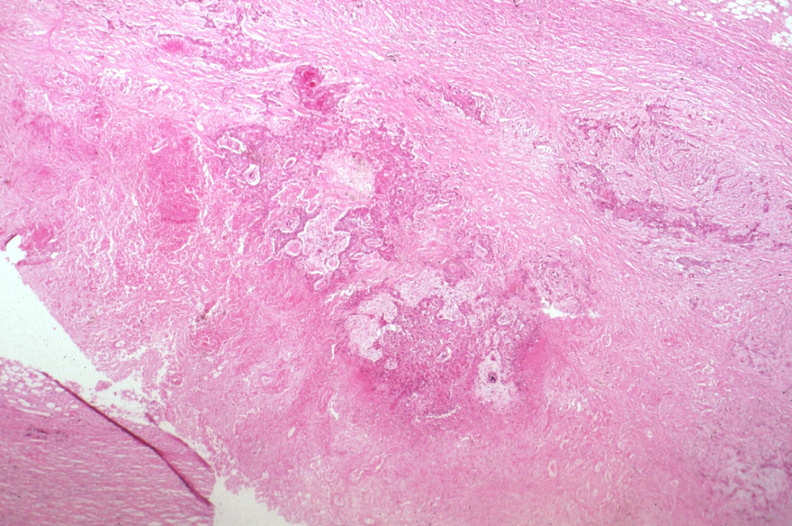

HISTOLOGY: RESPIRATORY: Lung: Carcinoma: Micro H&E low mag squamous cell carcinoma in dense fibrous stroma same case as 6